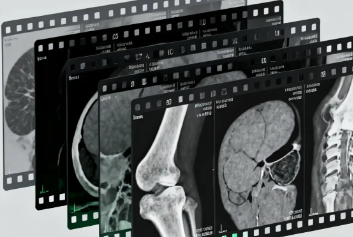

超声工作站/云胶片迈德卫医疗影像云-PACS不止是 “存影像”,更是诊断的 “加速器”去医院做 CT、核磁共振检查后,你是否好奇:那些黑白影像如何变成诊断依据?医生又如何快速调取几年前的检查报告?答案藏在一个看不见却至关重要的医疗大脑里 ——医学影像 PACS 系统。跟着超声工作站/云胶片迈德卫医疗影像云一起来了解下吧!在没有 PACS 的年代...